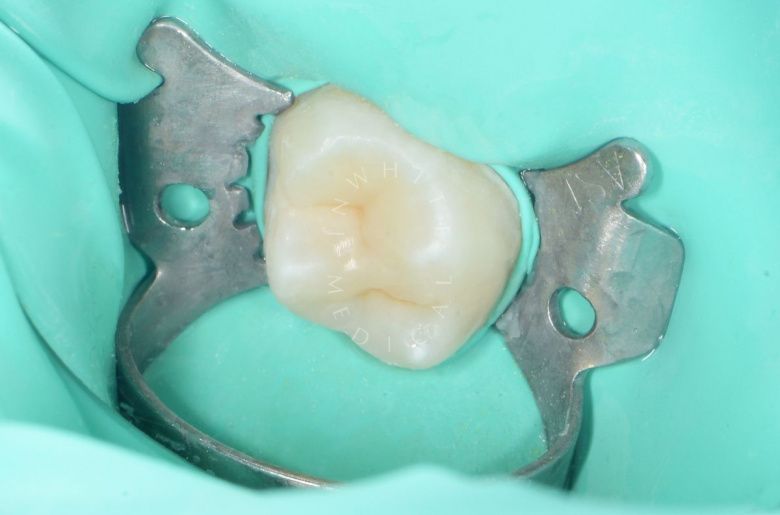

етская стоматология под наркозом Москва. Лечение молочных зубов и установка металлических коронок во сне - после процедуры